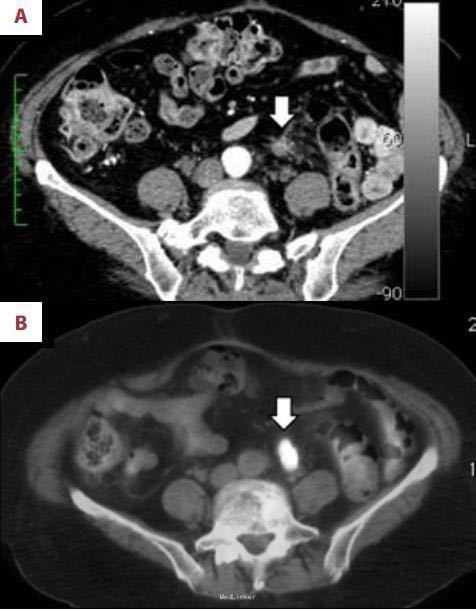

患者男性,69岁,5年前因大便带血于我院就诊,无其它不适主诉,结肠镜检查发现结肠肿瘤并肠腔狭窄,结肠镜无法通过。活检病理为高分化腺癌。CT检查示无浆膜侵袭和远处转移,临床分期为II期。行结肠癌根治术,周围淋巴结清扫。术后病理:癌灶已经侵蚀浆膜层,周围淋巴结未见转移征象,切缘阴性。术后患者每3个月来医院进行血生化复查,每6个月行腹部CT检查。 术后一年半后CT检查结果显示腹主动脉分叉处左侧见一边界模糊,非肿瘤性病灶,血供丰富(见下图1A)。考虑为术后结缔组织的炎症反应。随后几次复查发现该病灶的形态逐渐改变。术后三年CT检查结果显示病灶体积增大,但放射科医生依旧认为是良性病变(见下图1B)。最近来复查,上述病灶在CT上呈实性肿瘤样改变(见下图2A),怀疑为结肠癌术后局限性复发。但癌胚抗原和CA199都在正常范围内。为了明确诊断,患者去外院行FDG-PET/CT检查。检查结果如下图(2B),上述病灶呈明显高FDG摄取,除上述病灶外未发现其他存在病灶。

初步诊断为局限性结肠癌复发。随后患者行手术切除,病变位于左侧输尿管与腹主动脉及分支之间。术后标本肉眼观可见肿块由结缔组织组成,包括白色和坚韧的疤痕(下图3A)。组织病理结果显示为良性脂肪组织,包括纤维血管成分(下图 3B)。